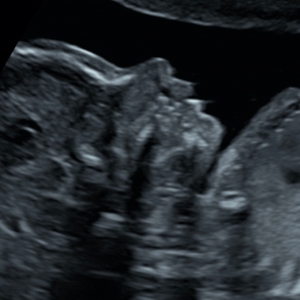

ÉCHOGRAPHIE OBSTÉTRICALE